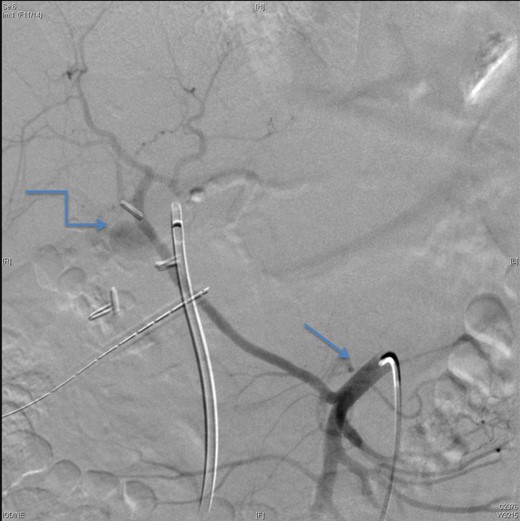

A CT scan showed replaced right HAP inside the collection (straight arrow).

An angiographic scan showed superior mesenteric artery (straight arrow) and replaced right HAP (angulated arrow).